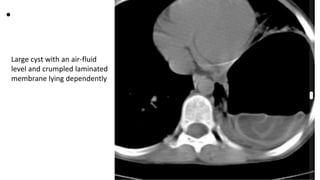

Large cyst with an air-fluid

level and crumpled laminated

membrane lying dependently

• Presents with cough and hemoptysis.

Large cavity with an air fluid level in